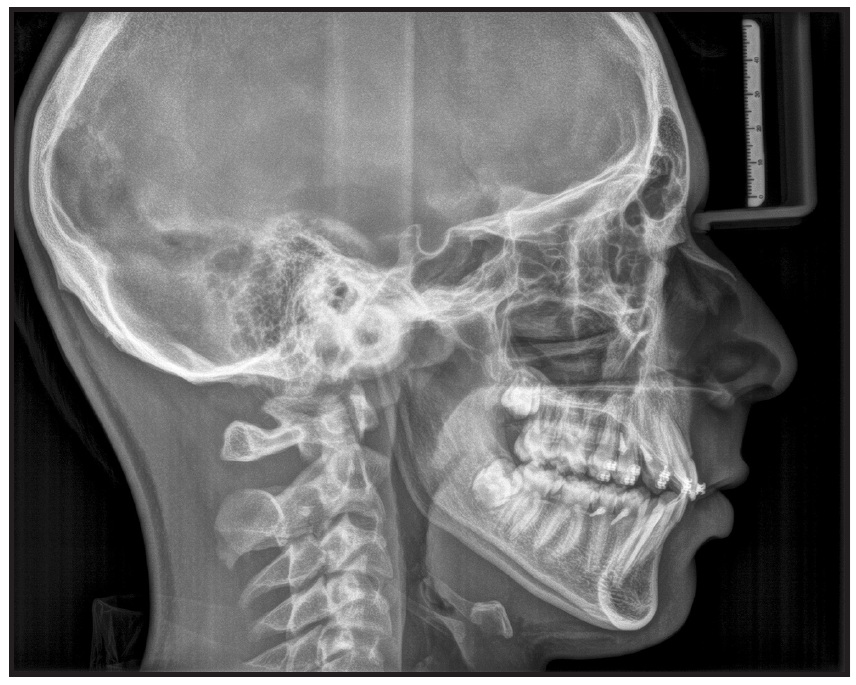

A 12-year-old male was referred by his dentist for orthodontic consultation. Clinical examination found a convex profile with a retrusive chin, excessive nasolabial angle, symmetrical mandible, and incompetent lips (Fig. 1).

Fig. 1 12-year-old male patient with retrusive chin, incompetent lips, skeletal Class II malocclusion, and palatally inclined upper incisors before treatment.

Cephalometric analysis indicated a skeletal Class II malocclusion with a long face, a short ramus, slightly palatally inclined maxillary incisors, and a protrusive inclination of the mandibular incisors relative to the mandibular symphysis (Table 1). The overjet and overbite were excessive.

Because of mild upper incisor flaring, there was no worsening of the profile during the Herbst treatment (Table 1). The A point advanced between pretreatment (T0) and post-Herbst (T1) cephalograms and remained almost unchanged thereafter. The upper first molars were intruded and distalized, and vertical dentoalveolar growth was well controlled. The maxilla grew downward and forward, so that the posterior intrusion had only a dentoalveolar effect. By the end of treatment, the upper first molars had returned nearly to their pretreatment positions. Lower incisor inclination was well controlled between T0 and T1 and between T1 and the end of treatment (T2). Pogonion advanced 4.5mm, and substantial growth occurred at the ramus as the articular point moved upward and slightly forward.

The H4T method we have described, involving TADs in both arches, provided satisfactory control of our patient’s vertical dimension (−2.9° change in SN/GoGn between T0 and T2). This induced a counterclockwise rotation of the mandible and contributed to a considerable mandibular advancement, as measured in a 4.5mm forward movement of pogonion on the cranial base superimposition (Fig. 7B).

Fig. 7 (cont.) B. Superimposition of cephalometric tracings before treatment, after Herbst therapy, and after treatment.